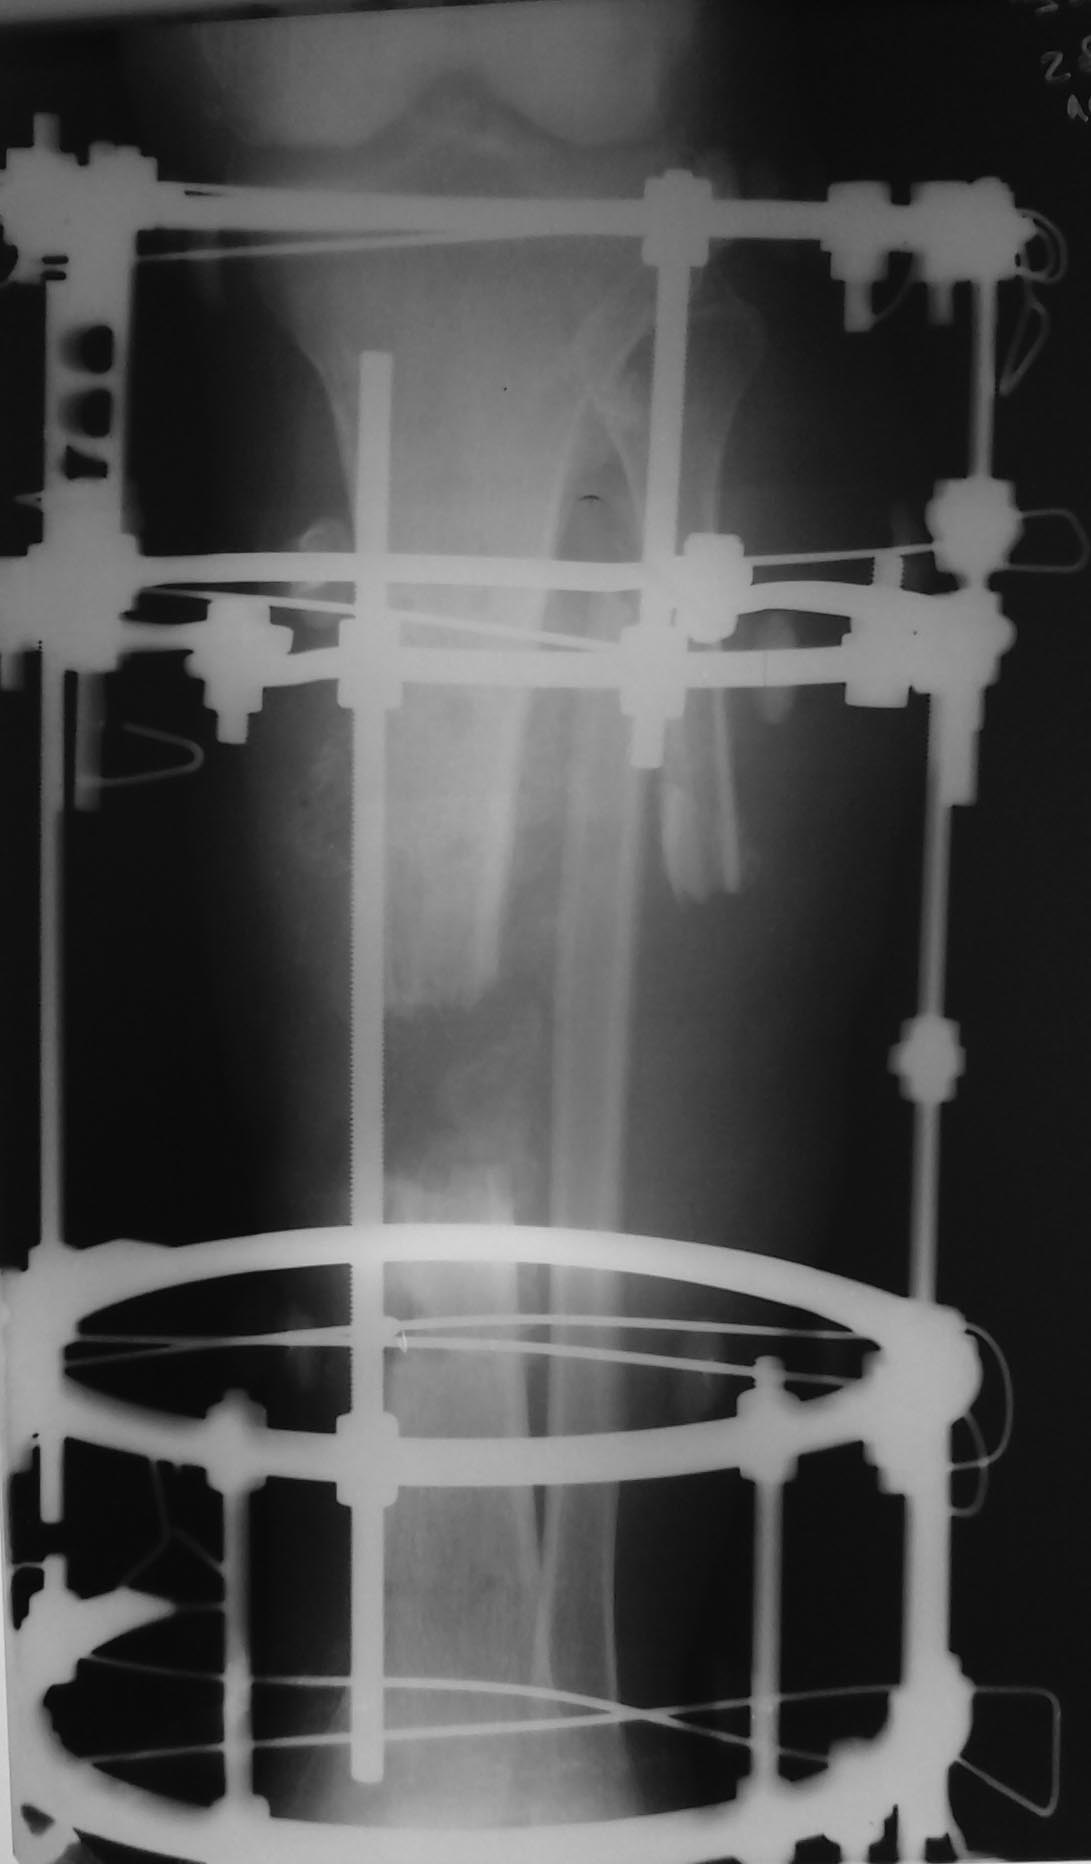

Коллеги! Прошу совета - как рациональное поступить. Пациент 65 лет, открытый перелом костей голени, травма плечевого сплетения на противоположной стороне. Травма 6 месяцев назад, ДТП. Открытый перелом голени в остром периоде был фиксирован стержневыми аппаратом, ввиду необходимости выполнения МРТ стержней аппарат был демонтирован, выполняла иммобилизация гипсовая лонгетой. После МРТ занимались нейрохирурги (остеосинтез шейный позвонков с костной пластиком аутокостью), после инфицирования перелома голени выполнены ВХО раны голени и ВЧО аппаратом Илизарова. Некроз мягких тканей голени 5%площади, неоднократно ВХО, в том числе -резекция большеберцовой кости (области перелома) в средне-нижней трети 7,0 см -на границе здоровых тканей, пластика раны местными лоскутами, интраоперационно с целью уменьшения площади раны в аппарате Илизарова произведено уменьшение дефекта бб кости и мягких тканей путем сближения промежуточных опор.

Полностью устранить дефект большеберцовой кости не удалось (галифе на голени, угроза некроза при контакте с опорой изнутри). Было достигнуто уменьшение дефекта до 4,0 см, укорочением голени стало до 3,0 см.

Рентгеновские снимки в аппарате Илизарова прилагаю.

4. Если есть свищи, значит есть остеомиелит.. На представленной р- гр видны участки остеолизиса. Зона резекции недостаточна. Её нужно увеличить.

В данном случае, сделал бы, спиральную КТ - можно оценить протяженность медуллярного поражения кости. Жаль, что в такой ситуации придётся демонтировать аппарат. А потребность в спиральной КТ - очевидна, видны участки лизиса кости от спиц дистально и проксимально.